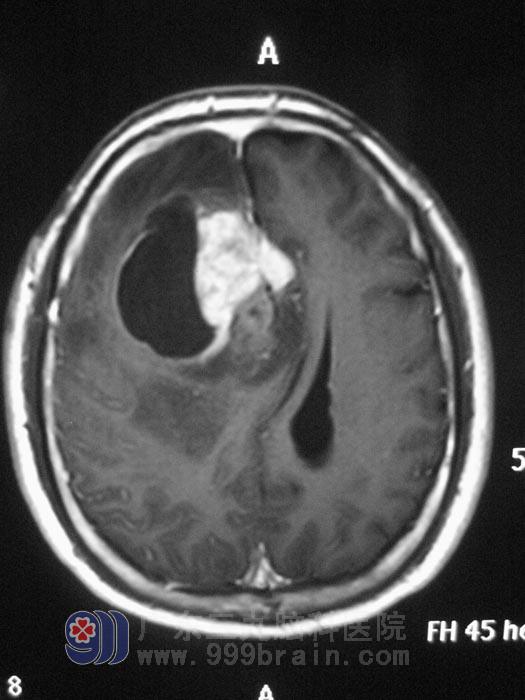

医生说,李先生是右额叶的4.0*4.0*5.0cm占位性病变,极有可能是胶质瘤,并且还告诉他,脑胶质瘤具有进行性发展和侵袭性生长的特性,属恶性肿瘤范畴,其治疗迄今仍是一世界性难题,由于肿瘤组织与正常组织之间界线不清,手术很难将其彻底清除,复发率极高。

2011年3月27日,来到广东三九脑科医院,他们对 综合神经外科的 鲁明主任说:“给我手术吧,瘫痪了我也认了,只要不昏迷。”3月30日,鲁主任主刀,在全麻下给李先生行右侧额叶占位切除术,术中见肿瘤呈褐灰色,质软,血运较丰富,边界不清,边止血边超声吸引吸除肿瘤,分块切除肿瘤,前至额极,内侧完全切除至大脑镰,见胼胝体,后近中央前回,底部见侧脑室前角,范围约4.0*4.0*5.0cm。术后李先生生命体征平稳,麻醉清醒顺利,四肢可见自主活动,病理检查回报:(右侧额叶)胶质母细胞瘤(WHOIV级)。http://www.999brain.com/

手术前影像